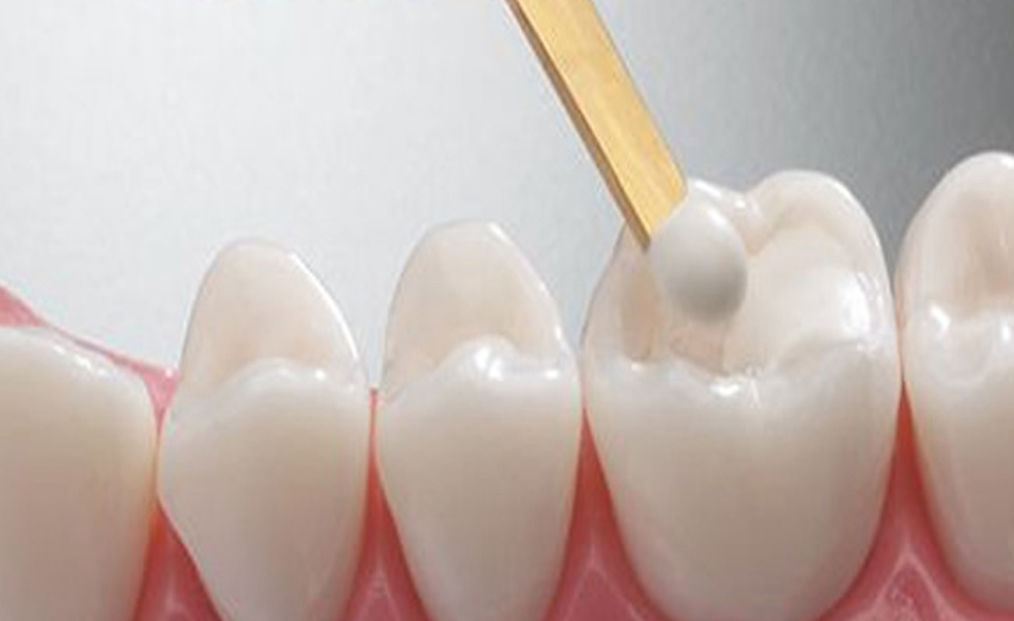

Restauracija zuba oštećenih karijesom. Nakon uklanjanja zaraženog tkiva, zub se nadoknađuje kompozitnim ili drugim savremenim materijalom, čime se obnavljaju funkcija, čvrstoća i estetski izgled zuba.

Redovni stomatološki pregledi omogućavaju pravovremeno otkrivanje problema i planiranje adekvatne terapije. Preventivne procedure, uključujući fluoridaciju i edukaciju o higijeni, pomažu u očuvanju zdravih zuba i desni, sprečavajući ozbiljnije intervencije i čuvajući prirodan izgled osmeha.